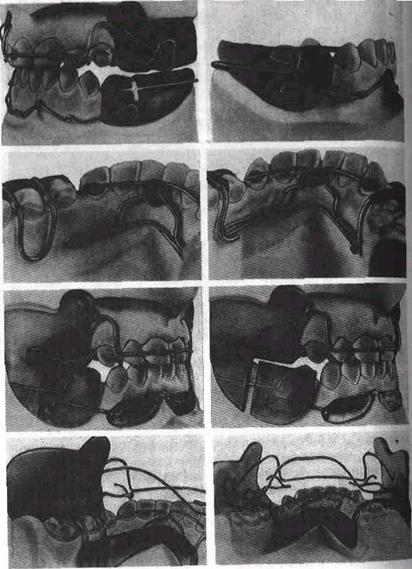

Рис 16 12 Этапы изготовления регулятора функций Френкеля I типа

Второй этап На прикусной валик воскового шаблона накладывают разогретые ленты воска толщиной 1, 5-2 мм приклеивают их расплавленным воском Восковой шаблон вви дят в рот и определяют конструктивный прикус Режущие края резцов устанавливают в краевом смыкании так, чтобы верхни

резцы минимально перекрывали нижние, а боковые зубы были разобщены При наличии сагиттальной щели, равной 8 мм или больше, нижнюю челюсть перемещают вперед на 5—6 мм Модели челюстей, составленные с помощью воскового шаблона в конструктивном прикусе, загипсовывают в окклюдаторе или фиксаторе Грота. После затвердения гипса прикусной шаблон удаляют.

Третий этап— изготовление и припасовывание регу­лятора функций При получении оттисков с челюстей переход­ная складка слизистой оболочки с вестибулярной поверхности альвеолярного отростка растягивается краем ложки, оттискным материалом и сглаживается, в связи с чем ее глубина и объем отображаются неточно. Гипсовую модель нижней челюсти кор­ригируют в переднем участке в области переходной складки слизистой оболочки путем ее гравировки вертикально и вниз на глубину 5 мм по обе стороны от уздечки губы Боковые щиты должны способствовать развитию апикального базиса зубной дуги в трансверсальном направлении Модель верхней челюсти гравируют в области первых премоляров и клыков, иногда в области бугров верхней челюсти на уровне переходной складки слизистой оболочки При повороте нижних клыков вокруг оси гравируют язычную поверхность коронок клыков, чтобы уси­лить давление лингвальной дуги на них и способствовать ис­правлению их положения. Если нет трем между зубами, то гравируют модель челюсти в области контактных пунктов межцу ГУ III II | II III IV или 4 3 2 I 2 3 4. а также между 6_V | V 6 или 6 5 I 5 б (при наличии вторых постоянных моляров — между 7 6 | 6 7) на толщину проволоки (0, 9—1 мм) Это необходимо для того, чтобы лингвальная и небная дуги, проволочные петли на клыки и небный бюгель при их перегибе с вестибулярной стороны альвеолярного отростка на небную или подъязычную располагались между соответствующими зубами, способствова­ли наилучшей стабилизации аппарата и дистальному переме­щению верхних зубов (рис 16 13, 16 14).